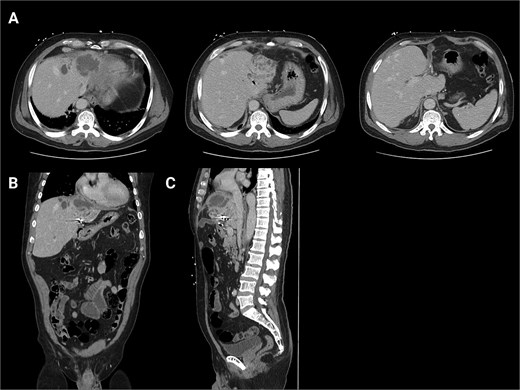

A 62-year-old male presented with the chief complaints of fevers, fatigue, and body aches for one week. He reports an ostomy placed fifteen years prior to, “drain the rocks from my liver.” He reports that stones drained from the ostomy for two years after it was placed. Physical exam was notable for abdominal incisions and left upper quadrant ostomy. Initial workup found a WBC count of 14 000×103/μl, alkaline phosphatase of 571 U/L, and normal bilirubin. Given his vague abdominal pain and fevers, a contrasted computed tomography (CT) scan of the abdomen was performed. This confirmed that the ostomy was a conduit from the biliary tree to the skin. It additionally found a 6.6 × 6.4 cm intrahepatic abscess (Fig. 1). He was admitted and was started on IV antibiotics. Gastroenterology (GI) and Interventional Radiology (IR) were consulted for endoscopic or image-guided drainage, but these were deferred given the tortuosity of his conduit and lack of a safe window, respectively. Given he had improved on antibiotics, it was deemed that operative intervention was not indicated at that time. He was transitioned to oral antibiotics, scheduled for outpatient endoscopic retrograde cholangiopancreatography (ERCP) to better delineate the biliary anatomy, and discharged. Of note, this institution’s policy is that Advanced Endoscopists perform ERCPs. At this time, there are no surgeons who performed ERCPs.

Initial CT scans. (A) Axial images progressing from superior to inferior. These show the hepatic abscess as well as the small bowel limb anastomosed to the biliary tree. (B) The same scan, but in a coronal view. (C) The same scan, but from a sagittal view. This view again illustrates the limb of a small bowel anastomosed to the biliary tree. Surgical clips are seen in the gall bladder bed.